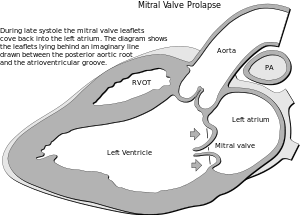

| In mitral valve prolapse, the leaflets of the mitral valve prolapse back into the left atrium. | |

The mitral valve, so named because of its resemblance to a bishop's mitre, is the heart valve that prevents the backflow of blood from the left ventricle into the left atrium of the heart. It is composed of two leaflets, one anterior and one posterior, that close when the left ventricle contracts.

Each leaflet is composed of three layers of tissue: the atrialis, fibrosa, and spongiosa. Patients with classic mitral valve prolapse have excess connective tissue that thickens the spongiosa and separates collagen bundles in the fibrosa. This is due to an excess of dermatan sulfate, a glycosaminoglycan. This weakens the leaflets and adjacent tissue, resulting in increased leaflet area and elongation of the chordae tendineae. Elongation of the chordae tendineae often causes rupture, commonly to the chordae attached to the posterior leaflet. Advanced lesions—also commonly involving the posterior leaflet—lead to leaflet folding, inversion, and displacement toward the left atrium.[12]

Echocardiography is the most useful method of diagnosing a prolapsed mitral valve. Two- and three-dimensional echocardiography are particularly valuable as they allow visualization of the mitral leaflets relative to the mitral annulus. This allows measurement of the leaflet thickness and their displacement relative to the annulus. Thickening of the mitral leaflets >5 mm and leaflet displacement >2 mm indicates classic mitral valve prolapse.[12]

Prolapse occurs when the mitral valve leaflets are displaced more than 2 mm above the mitral annulus high points. The condition can be further divided into classic and nonclassic subtypes based on the thickness of the mitral valve leaflets: up to 5 mm is considered nonclassic, while anything beyond 5 mm is considered classic MVP.[12]